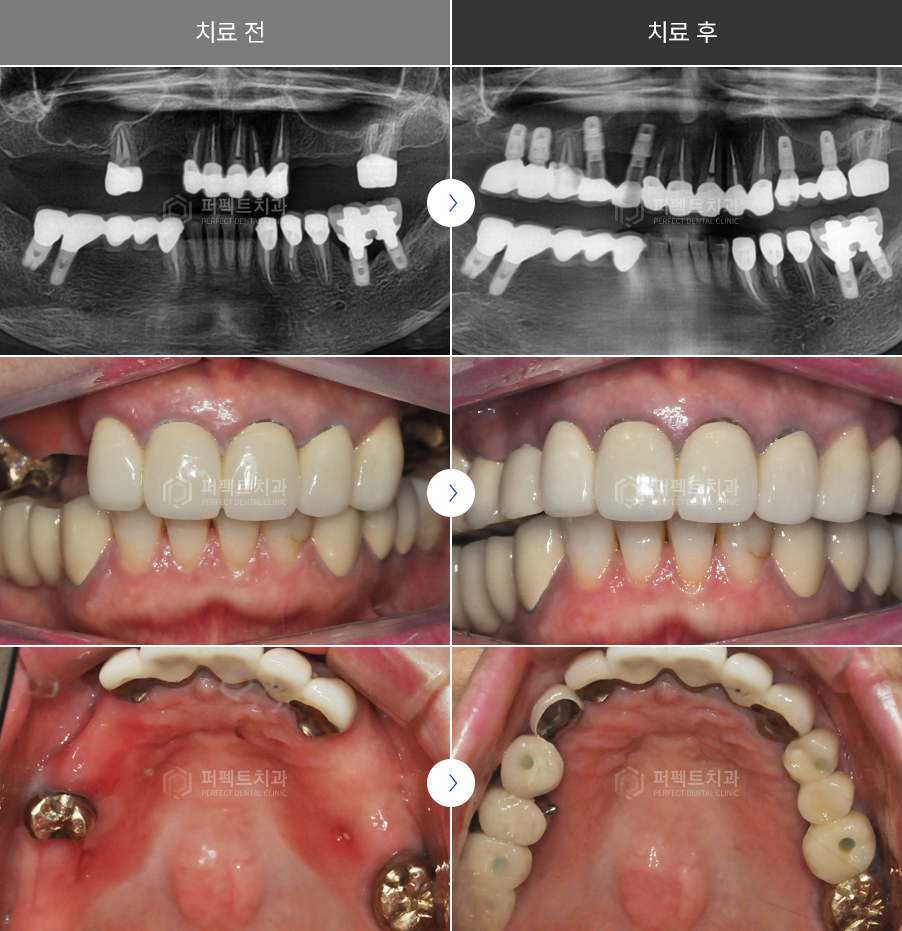

상악동거상술 치료증례

"60대 상악동수술 동반 임플란트"

틀니가 불편하고 기능적으로도 만족스럽지 못해

임플란트로 재치료를 희망하여 내원하셨습니다.

치료 전

세 부위에 수술이 필요할 것으로 보이고, 상악 우측은 임플란트를 심기에는 치조골의 양이 너무 적어서 상악동 내부 뼈이식이 필요했습니다.

다수의 치아를 대신해 임플란트를 여러 개 식립할 때

최종적인 기능을 할 수 있도록 좋은 위치에 심어야 합니다.

또한 남아있는 뼈가 얼마나, 어느 방향으로 남아있는가에 의해 거의 100% 결정된다고 해도 과언이 아닙니다. 뼈가 다 녹은 다음에 좋지 않은 위치에 심어서 보철을 힘들게 맞추기 보다는 치아를 상실하고 최대한 빠른 시간 안에 적절히 뼈가 있을 때 임플란트를 심어서 좋은 결과를 도모하는 것이 환자분의 만족도를 높일 수 있는 가장 좋은 방법이라고 할 수 있습니다.